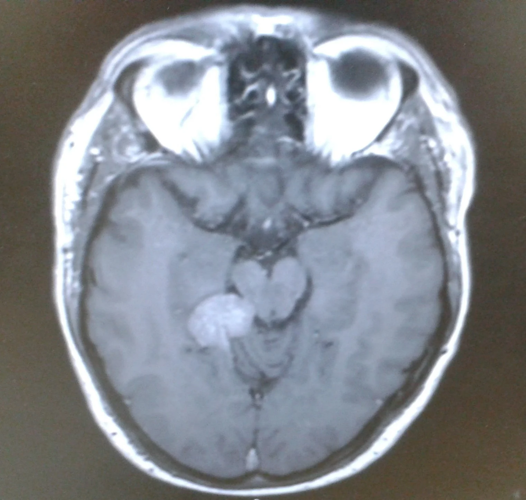

Darren Harris's brain scan. (Brain Tumor Research via SWNS)

He was sent for further treatments and MRIs which revealed he had been living with an inoperable tentorial meningioma – a slow-growing, low-grade tumor at the base of his brain.